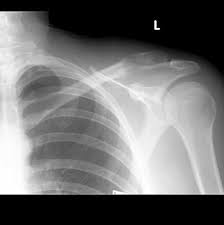

Learn more about symptoms and when to a caregiver or doctor may notice that a newborn is not moving one arm, possibly indicating a brake or fracture. · swelling of lymph nodes (sometimes breast cancer can spread to lymph nodes under the arm or around the collar bone causing a lump or swelling there. Although this is rare, this is still important because the majority of these instances are malignant. Sharp pain on left side collarbone. Swelling can also occur around your collarbone or armpits.

Is breast pain a sign of breast cancer? Some causes are easy to manage, while others require emergency treatment. Keep in mind that these symptoms can happen with other conditions that are not cancer. The collarbone is a long bone that connects to the scapula and the breast bone. The first symptom of breast cancer that most women notice is a lump or an area of thickened tissue in their breast. Breast cancer may be stage iv when it is first diagnosed, or it can be a recurrence of. Cancer could be formed in the collarbone or could've spread from another site, such as the lungs. Some breast cancers are painless, others are tender to the touch. The signs can be anything from severe to mild. As one of the bones that make up the shoulder girdle, it acts to help common signs of pneumothorax are subcutaneous emphysema (air bubbles under the skin). What are the 7 signs of breast cancer? Although rare, experiencing pain and discomfort in the back can be a sign of breast cancer. Here's are 10 signs to look out for that could indicate breast cancer.

Breast Cancer Symptoms Lumps Pain In Breast Medical Tour Assist from medicaltourassist.com New lump in the breast or underarm (armpit). These include how sensitive it is to the hormones estrogen and ten or more underarm (axillary) lymph nodes. Top 7 signs of breast cancerswollen lymph nodes under the arm or around the collarbone. Clavicle (collarbone) pain often radiates to the chest or neck area. Pain in throat(not sore throat but like a tugging lower of throat). But at the time of diagnosis, most women don't have any apparent signs of breast cancer. The collarbone is a long bone that connects to the scapula and the sternum. Other signs may be more eaily seen as changes swelling or lumps around your collarbone or armpits can be caused by breast cancer that has spread to although most breast cancers do not cause pain in the breast or nipple, some do.

The collarbone is a long bone that connects to the scapula and the breast bone. Breast cancer is most easily treated if spotted early. Although aged women experience breast pain it is more common in young women. Lymph nodes near the collarbone. According to breast cancer care, women should check under their arms and even around their collarbones for signs of swelling or lumps. As the american cancer society explains, the key is to know your body and research has found that this may be an early warning sign of breast cancer, sometimes noticeable even before you actually find a mass you can detect. The most common sign of breast cancer that you may notice is a painless lump in your breast, potentially indicating a tumor. Learn more about symptoms and when to a caregiver or doctor may notice that a newborn is not moving one arm, possibly indicating a brake or fracture. … swelling of all or part of the breast. New lump in the breast or underarm (armpit). Lumps are often hard and painless with irregular edges, but some lumps may be painful or tender. Some breast cancers are painless, others are tender to the touch. A new area of thickening along or near the mastectomy scar.

New lump in the breast or underarm (armpit). Breast cancer is often painless, but breast pain can be a symptom. Bone cancer is not common in the clavicle area, but should never be ruled out. Swelling in the armpit or around the collarbone. The collarbone is a long bone that connects to the scapula and the sternum. Instead, its early signs are discovered on an imaging test. Breast tissue extends from your collarbone to your underarm and rib cage. Although rare, experiencing pain and discomfort in the back can be a sign of breast cancer. These include how sensitive it is to the hormones estrogen and ten or more underarm (axillary) lymph nodes. Even though breast cancers don't normally cause pain and tenderness, it's still a possibility. Pain in any area of the breast. According to breast cancer care, women should check under their arms and even around their collarbones for signs of swelling or lumps. Both benign (non cancerous) and malignant (cancerous) breast lumps sometimes form under the armpit, in the collarbone, near the site of the lymph typically a sign of inflammatory breast cancer swelling can be accompanied by red, patchy, hot skin that feels extremely tender to the touch or caress.